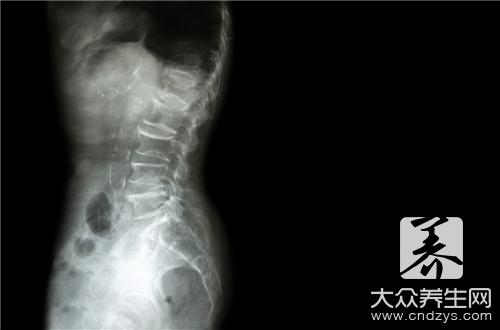

病因病机 跖腱膜是维持足纵弓的组织结构,它起于跟骨跖面结节,向前伸展,在跖骨头附近分成五段,分别附着于足趾近侧趾节上。趾短曲肌附着其深面。 跖趾关节背屈,趾短屈肌的收缩,体重的下压等三重力量集中作用于跟骨跖面结节上,其受力相当大。长期、持续、过大的牵引刺激,可以在跟骨跖面结节的跖腱膜附着处发生慢性(退变性)损伤,产生骨膜炎或纤维织炎。

先天不足或后天失养,及年龄增加等因素引起体质下降,各组织器官退行性改变,足力虚弱,韧带松弛,导致足弓的降低,跖腱膜所受张力增加,起点处受到的牵拉力更集中、更强大。因此,年老体或衰是发生跟痛症的根本原因。所以,跟痛症多发生于中年以后。如再遇体重骤增;体质降低;突然步行过多;长时间站立;穿鞋子不合适等原因,则可引起跟痛症的发生。跖腱膜附着处在长期、持续、过大的张力刺激下,可以出现钙质沉着,以增加韧带强度,抵抗日渐增大的牵引力(表现为骨刺形成)。